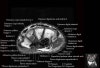

- Sagittal section

Sagittal T1 evaluates the tendons, bone marrow and relationships between the osseous structures.